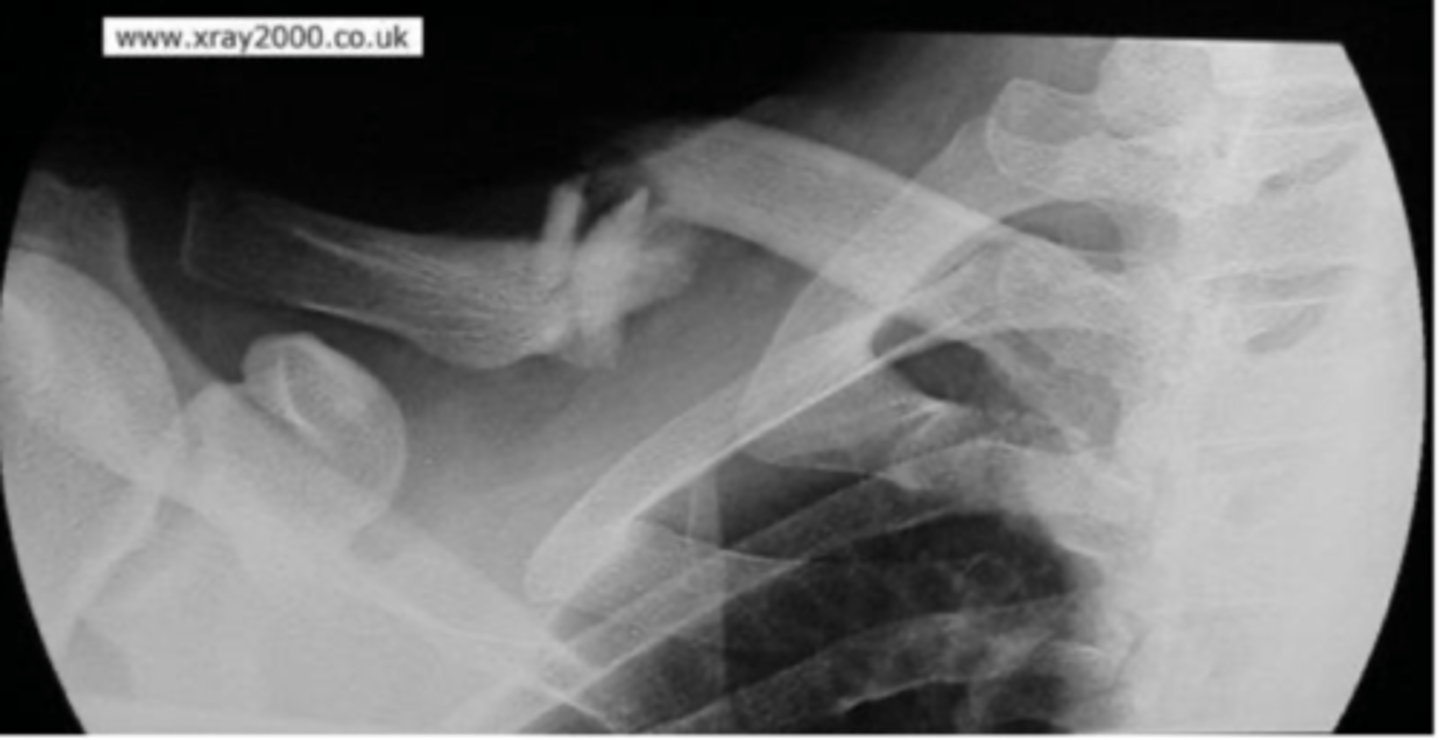

Axillary (Trauma)

What view is this?

Fracture of the humerus and inferiorly displaced

What is the issue?